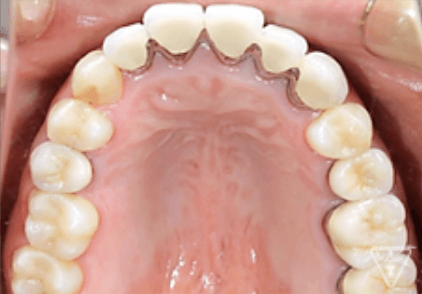

治療前